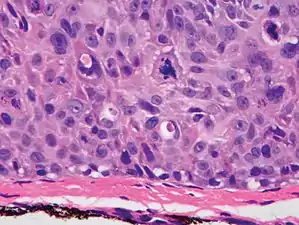

Histopathologically, the epidermis in cSCC in situ (Bowen's disease) will show hyperkeratosis and parakeratosis. There will also be marked acanthosis with elongation and thickening of the rete ridges. These changes will overly keratinocytic cells which are often highly atypical and may in fact have a more unusual appearance than invasive cSCC. The atypia spans the full thickness of the epidermis, with the keratinocytes demonstrating intense mitotic activity, pleomorphism, and greatly enlarged nuclei. They will also show a loss of maturity and polarity, giving the epidermis a disordered or "windblown" appearance.

Two types of multinucleated cells may be seen: the first will present as a multinucleated giant cell, and the second will appear as a dyskeratotic cell engulfed in the cytoplasm of a keratinocyte. Occasionally, cells of the upper epidermis will undergo vacuolization, demonstrating an abundant and strongly eosinophilic cytoplasm. There may be a mild to moderate lymphohistiocytic infiltrate detected in the upper dermis.[12]

Histopathology of squamous-cell carcinoma in situ (black arrow), compared to normal skin, showing marked atypia.

Squamous-cell carcinoma in situ, showing prominent dyskeratosis and aberrant mitoses at all levels of the epidermis, along with marked parakeratosis.[12]